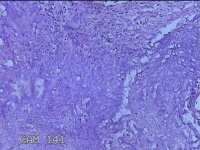

阑尾

性别

女

年龄

48岁

临床诊断

急性坏疽性阑尾炎 弥漫性腹膜炎

一般病史

转移性右下腹疼痛3天。

标本名称

大体所见

灰白暗红色阑尾2.5x0.8x0.3cm一条,表面糜烂,肿胀,带大量系膜,部分已切开,见腔内暗红色,另有灰褐色粪石1.9x0.7x0.3m一枚。